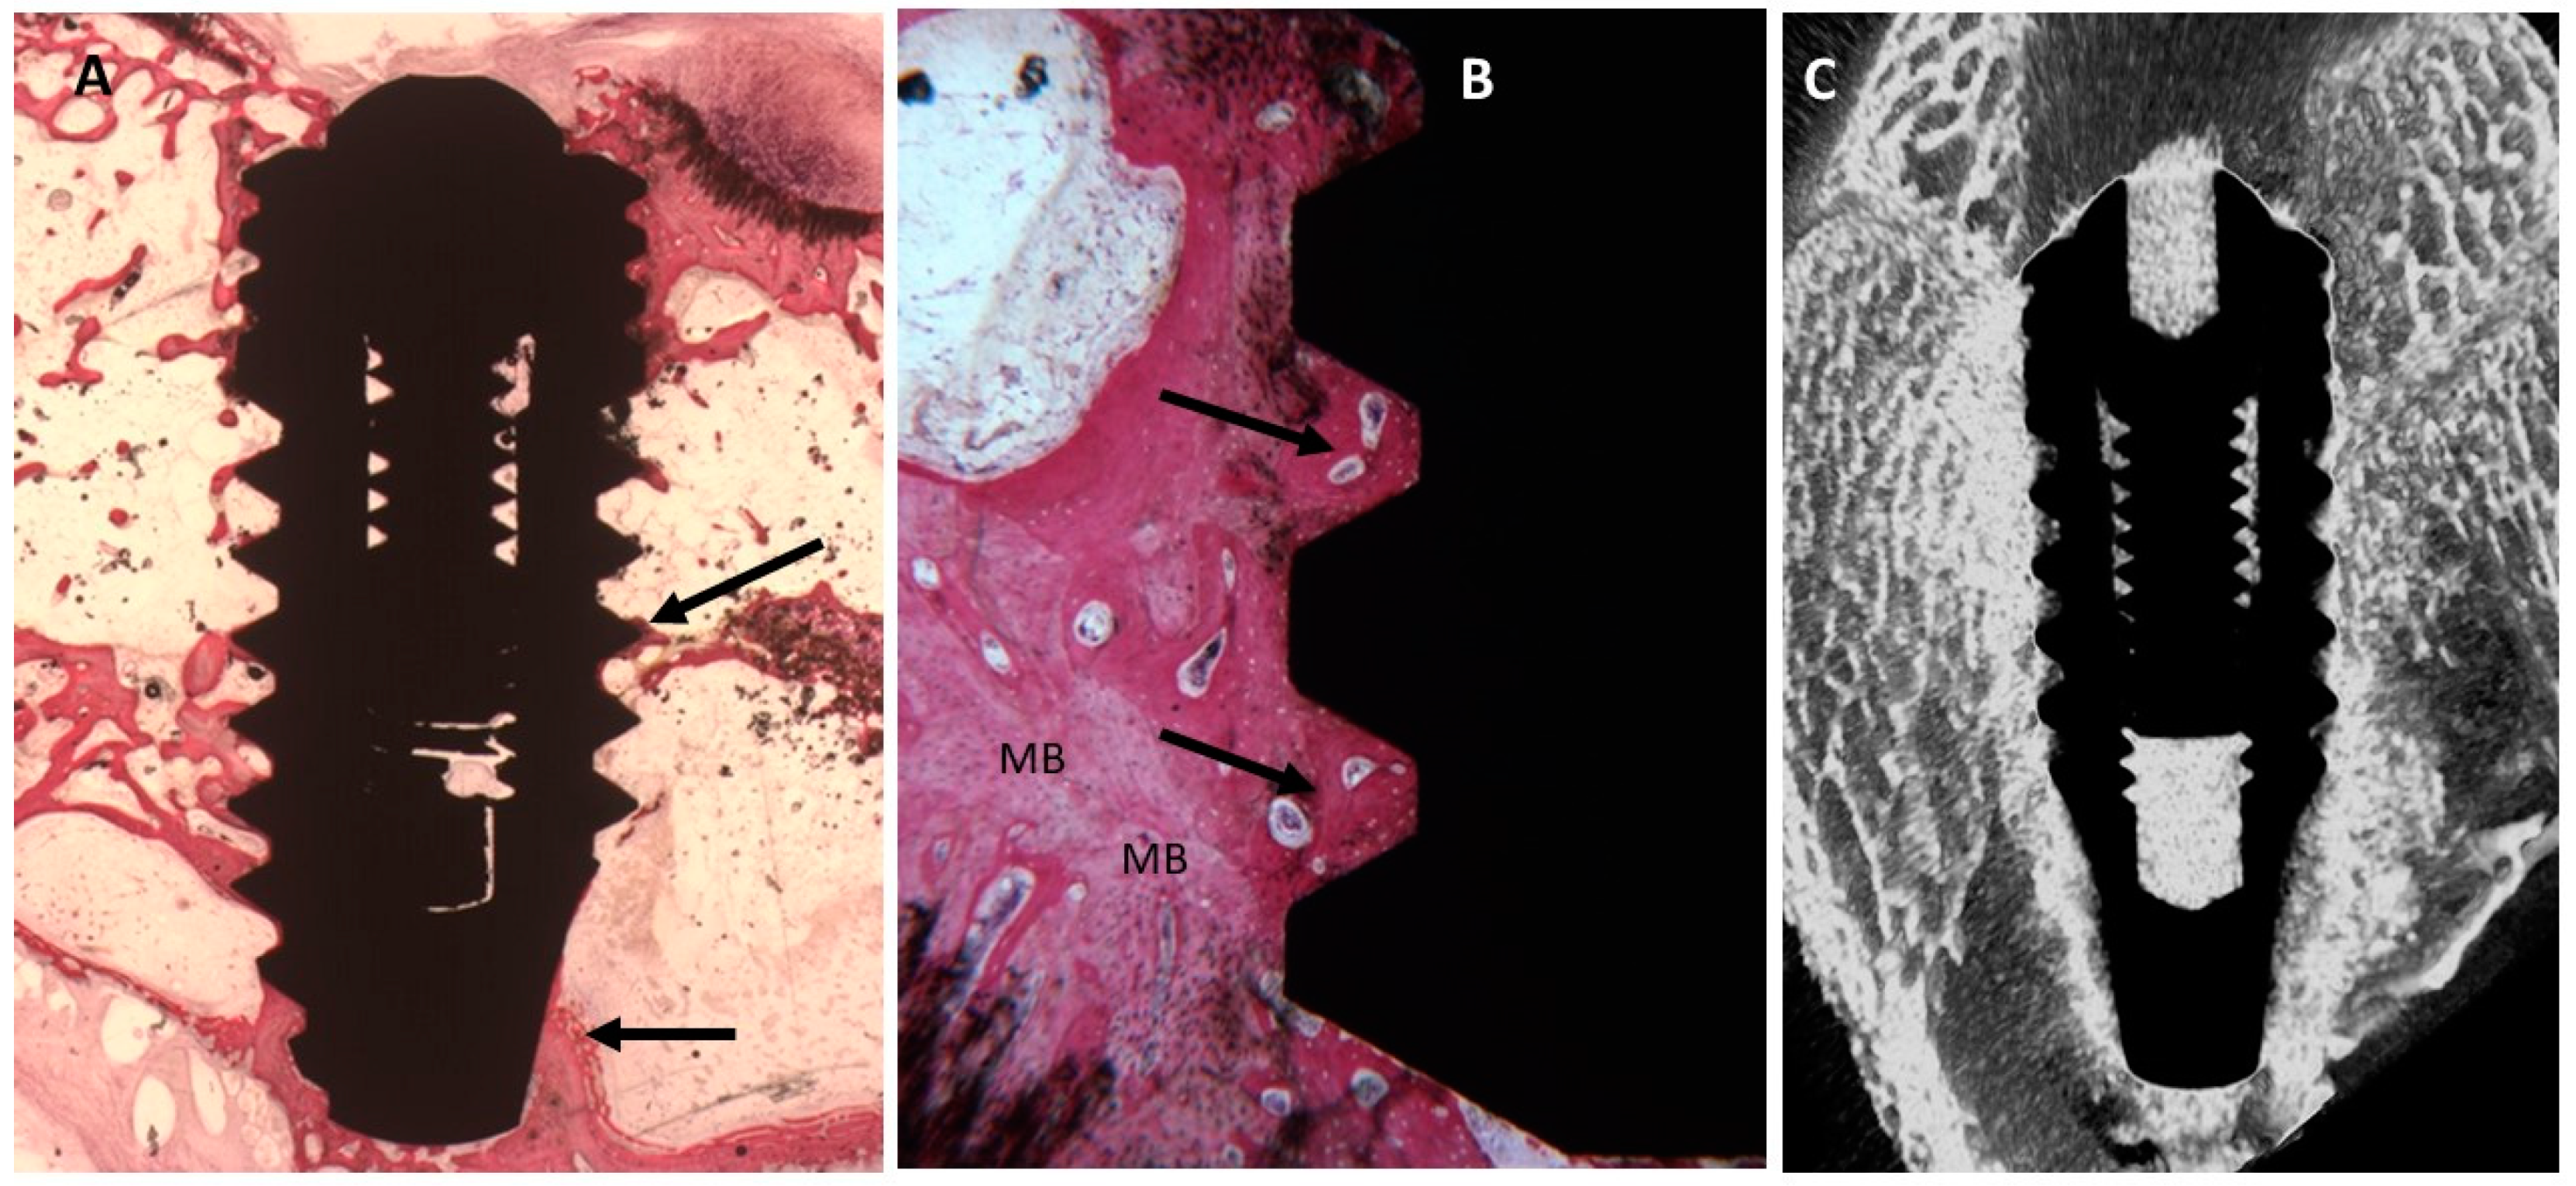

2.3. Micro-CT Evaluation

2.4. Histological Evaluation

2.4.3. Sixty Days

Uncoated Implant Surface

Collagen-Coated Surface